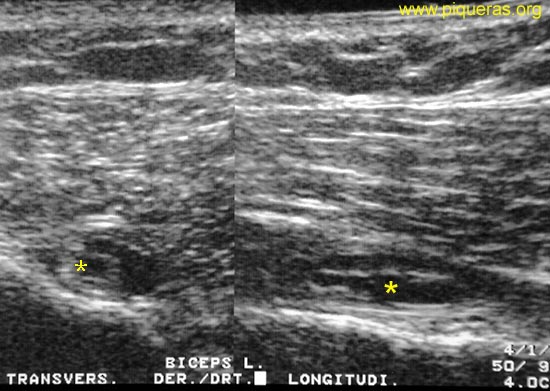

Rotura

interna longitudinal del Bíceps (derecho).

Mujer de

65 años. Omalgia derecha, predominio anterior

tras pequeño esfuerzo.

Se observa

una imagen líquida fusiforme longitudinal intratendinosa

en bíceps.